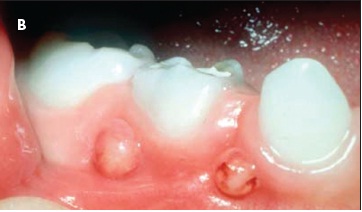

| The Pathophysiology of Dental Caries: A Brief Review The cause of early childhood caries (ECC) is multifactorial, but the 2 main culprits that interact at the tooth surface to produce ECC are dietary sugar and bacteria—particularly Streptococcus mutans. Infants are known to acquire S mutans from their mothers or primary caregivers in the first 2 years of life.29,30 Exposure to sugary drinks from a bedtime bottle or frequent consumption of carbonated soft drinks31 places young children at increased risk for dental decay. The acidic by-products of the bacterial metabolism of sugary substances lead to the development of plaque. Plaque adheres to the tooth surface and causes dental demineralization or the leaching out of important minerals (ie, calcium, phosphate, and carbonate) (A). ![]() Untreated dental caries can lead to periodontal abscesses (B). Because of the adjacent location of anatomic structures, facial cellulitis (C) and maxillary sinusitis may result from direct extension of the odontogenic infection, which causes tissue breakdown and bone resorption.32 Further extension of this infectious process could potentially affect intracranial structures, leading to brain abscess or orbital cellulitis. Untreated odontogenic infections can also lead to Ludwig angina—a rare severe condition involving extension of infection into the floor of the mouth and beyond, with potential airway compromise.33 ![]() As with all odontogenic infections, the most common causative agents are anaerobes and Streptococcus and Staphylococcus species. A patient with signs and symptoms of Ludwig angina (neck and/or mouth pain and swelling, trismus, fever, malaise, fetid breath) must be treated emergently to ensure a secure airway. Surgical debridement as well as administration of broad-spectrum antibiotics with adequate anaerobic coverage provide definitive treatment.33 ![]() |